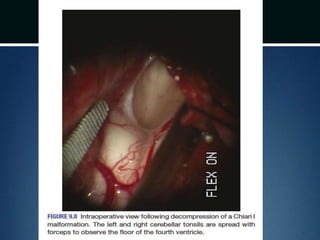

Posterior fossa decompression..

โ€ข Dura opened

โ€ข Arachnoid adhesions obstructing flow

removed and the floor of the 4th ventricle

examined

โ€ข Portion of occipital pericranium harvested

through a separate incision and duroplasty

performed

Posterior fossa decompression.. โ€ขDura opened โ€ข Arachnoid adhesions obstructing flow removed and the floor of the 4th ventricle examined โ€ข Portion of occipital pericranium harvested through a separate incision and duroplasty performed